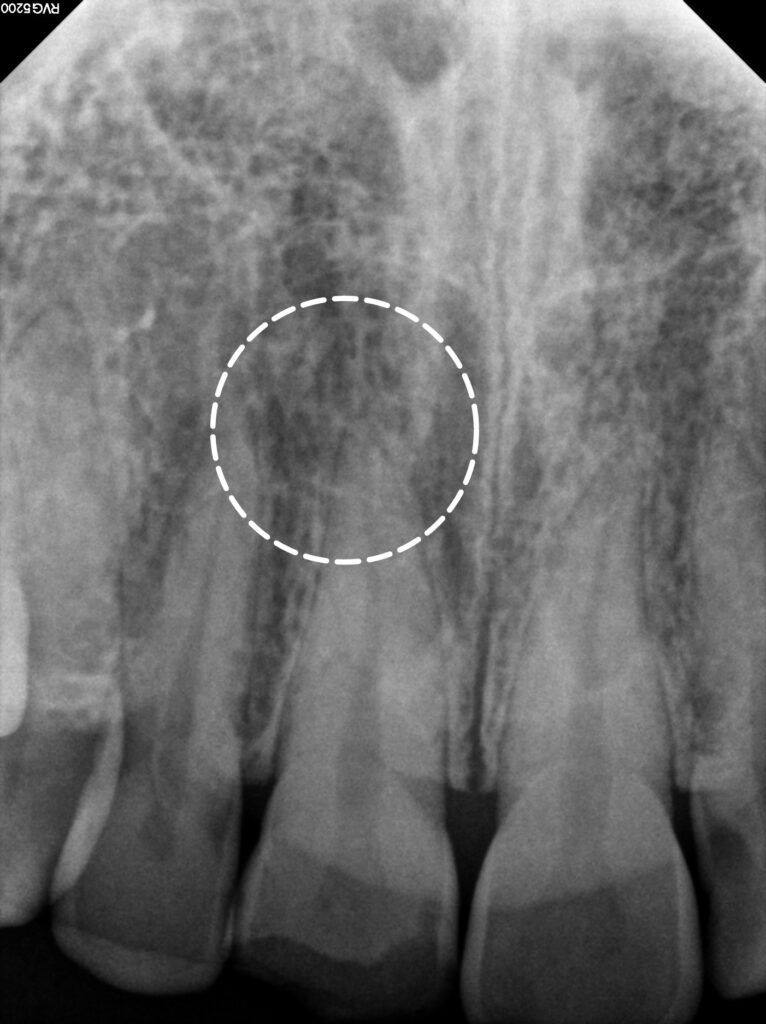

엑스레이 검사에서는

치근의 손상은 관찰되지 않고

주변 골조직도 정상 소견을

보이고 있습니다.

외상 후 3개월간의

경과 관찰 결과를 보았을 때

통증이나 불편감 없이

안정적인 상태를 유지하면서,

치수 활력 검사에서도

정상적인 반응을 지속적으로 보이고,

방사선 사진에서도

특별한 이상 소견은 없으면서